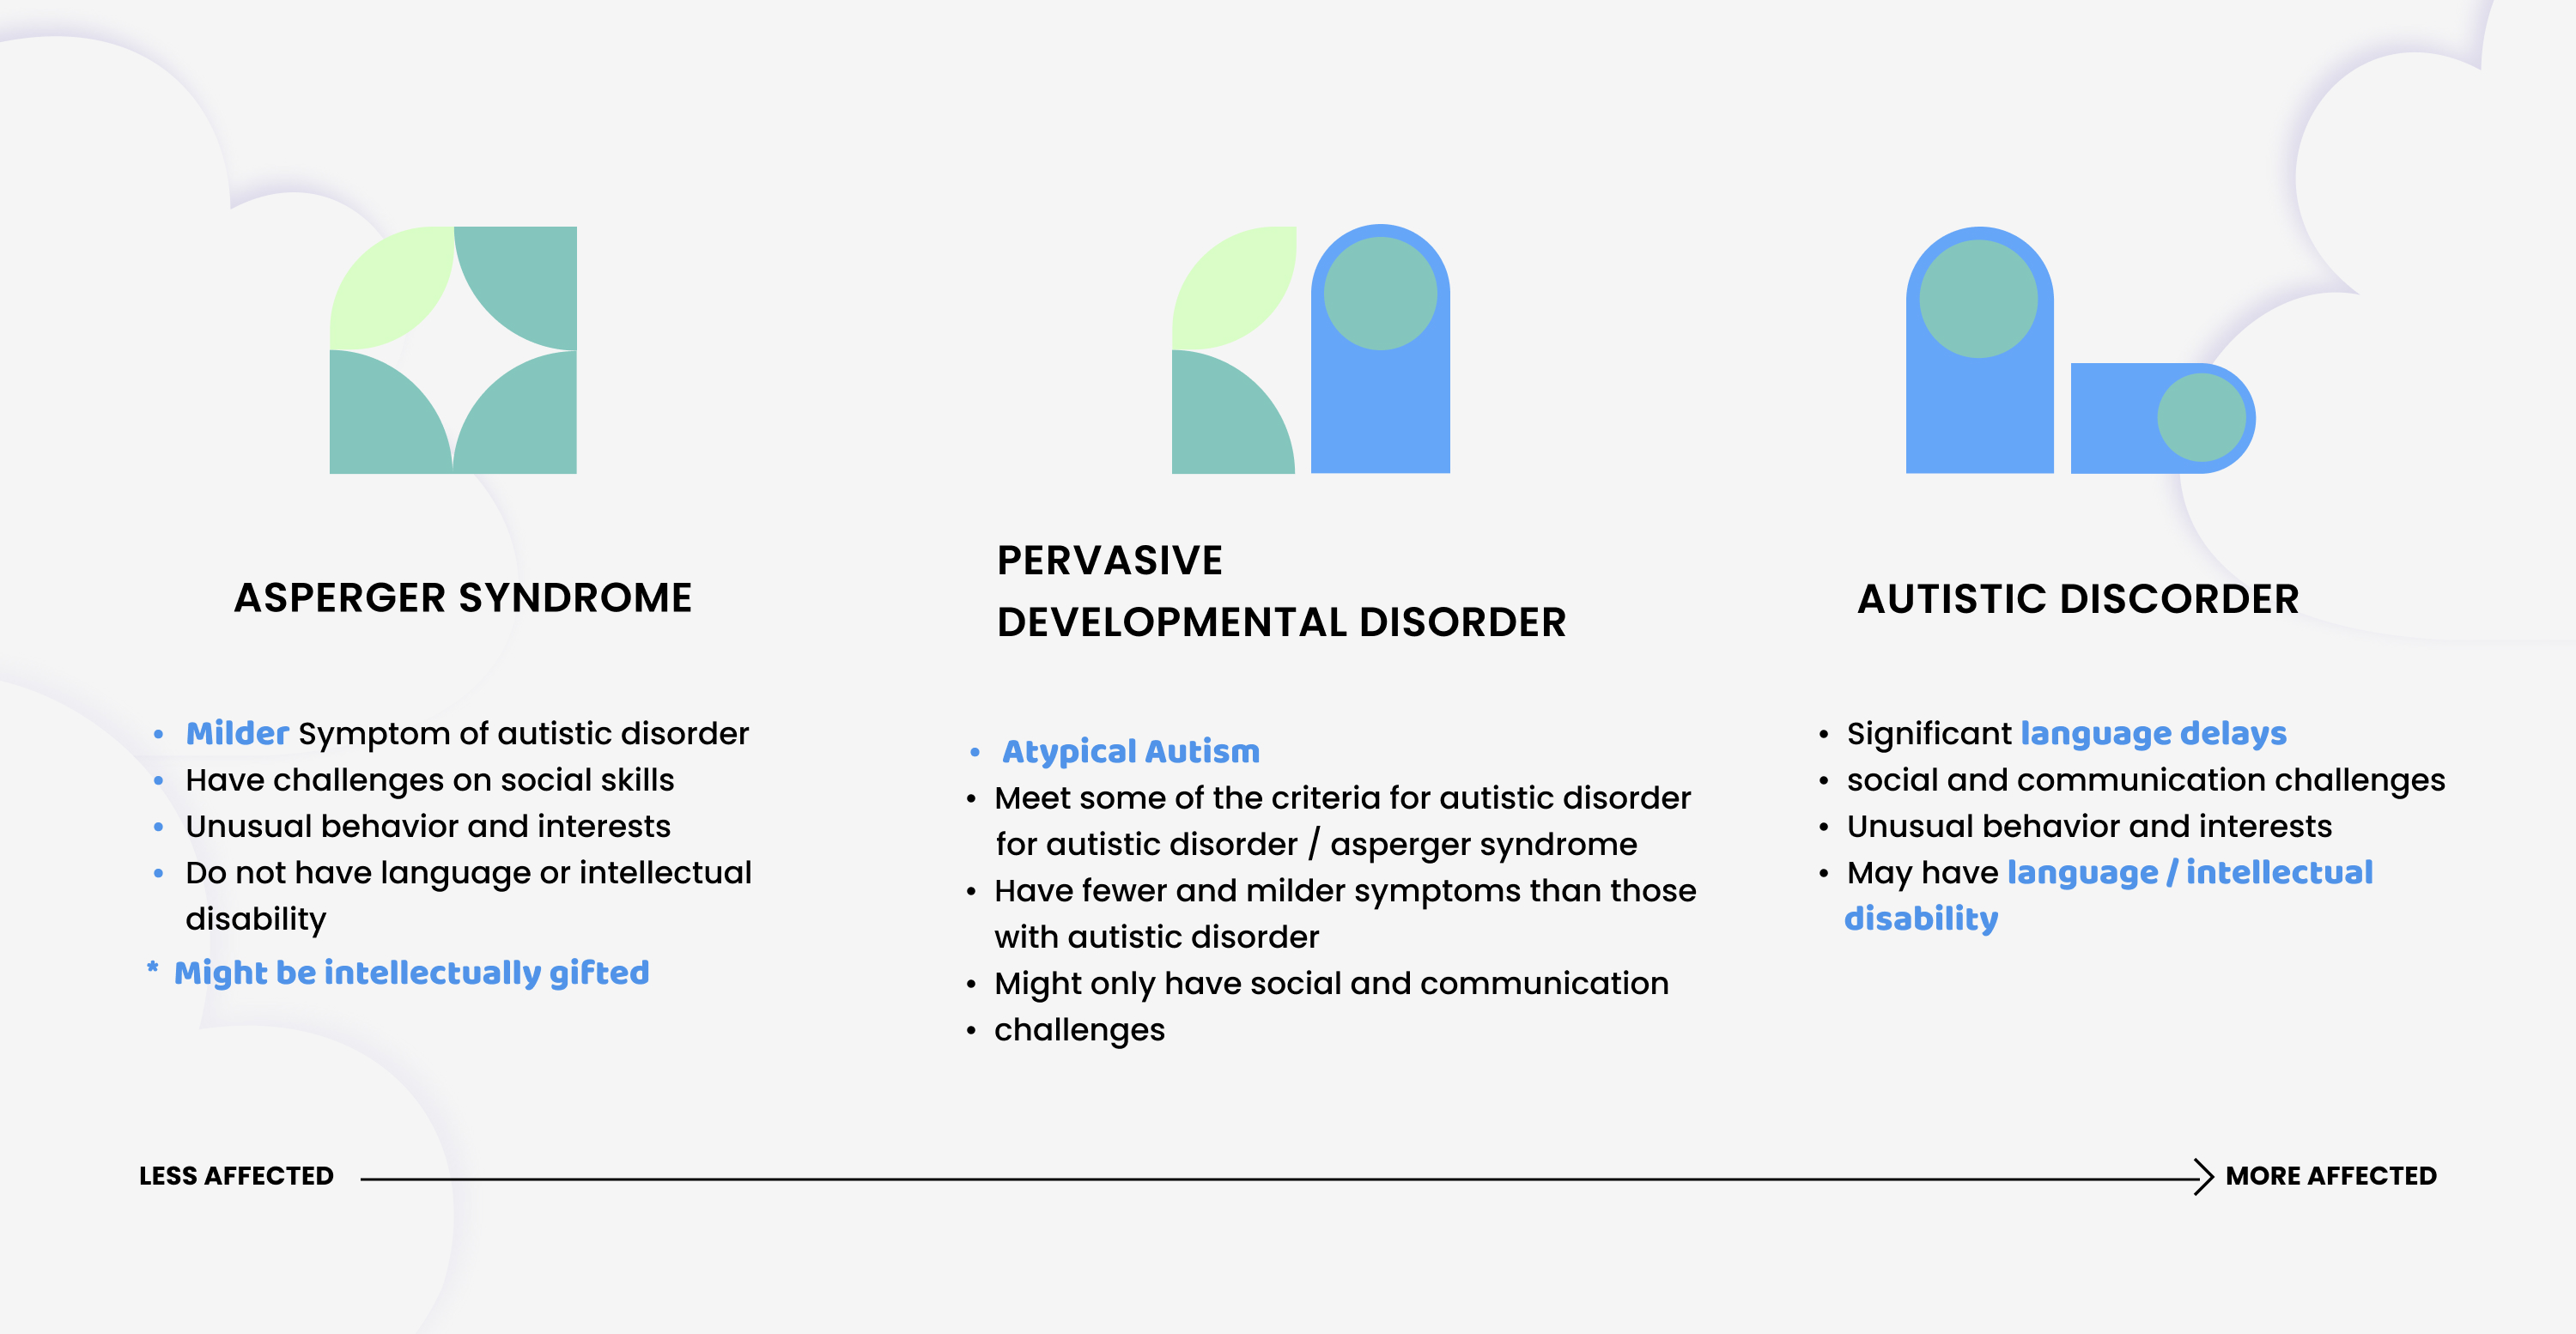

1. ASD is a developmental disability that causes social, communication, and behavioral challenge. Individuals with ASD have significant variations of symptoms.